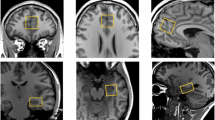

Single voxel 1H-MRS was acquired using the Point RESolved technique (TR = 3000 ms, TE = 30 ms, 96 averages, Vector size = 2048, Bandwidth = 2500 Hz). Prior to acquisition of the MRS the B0 homogeneity across the voxel was optimised automatically then fine-tuned manually using the first-order shim gradients to achieve a water linewidth of 18 Hz or less. A voxel measuring 20 × 20 × 20 mm was positioned in the ACC, in the midline immediately anterior to the genu of the corpus callosum (see Supplementary Fig. 1 for voxel placement and example spectrum). A second voxel measuring 20 × 20 × 15 mm was placed in the left hippocampus, angled parallel to the anterior horn of the temporal lobe and positioned just posterior to the amygdala, taking care to avoid the petrous bones (see Supplementary Fig. 2 for voxel placement and example spectrum).